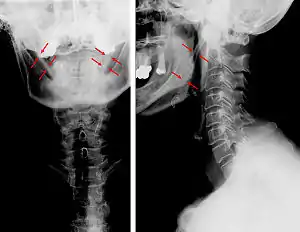

A Síndrome de Eagle é um conjunto de sintomas e sinais resultante da ossificação ou aumento do ligamento estilo-hióideo secundário a uma hipertrofia da apófise estilóide do osso temporal. Pode originar dor facial, otalgia, cefaleias, disfagia, odinofagia, zumbidos e muitas vezes trismo (contratura espasmódica do músculo masseter). O diagnóstico da Síndrome de Eagle é difícil. Os sintomas descritos acabam por ser atribuídos a outras causas. Os exames radiológicos nem sempre são conclusivos, se não forem específicos (incidências especiais) para investigação desta patologia. Muitas vezes estes doentes são considerados com sofrendo de patologia psicossomática e são encaminhados ao psiquiatra.[1]

A calcificação do ligamento do estilo-hióideo causa limitação dos movimentos cervicais e dores intensas na região. É uma causa importante de nevralgia secundária do glossofaríngeo. Aparece sobretudo na idade adulta e no sexo feminino. É raro antes dos 30 anos.[2] O diagnóstico é eminentemente radiográfico. O tratamento nos casos menos graves é feito com analgésicos. Por vezes, o paciente tem que ser assistido em cirurgia maxilo-facial já que na maioria dos casos o tratamento médico é ineficaz.[3]